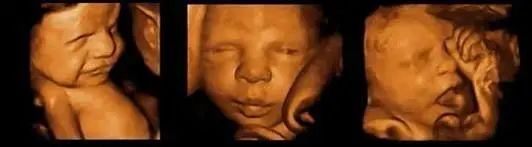

大排畸通常会在孕22~26周之间进行,主要是查看胎儿各个器官和系统的发育情况以及胎盘、羊水情况等,为的是检查胎儿有无畸形、是否健康。

大排畸通过影像学的手段不仅可以对胎儿大小进行一个检查,还能排查胎儿重大结构畸形,比如无脑儿、脑膜脑膨出、脊柱裂、严重胸腹壁缺损、单腔心、致死性软骨发育不良等等。